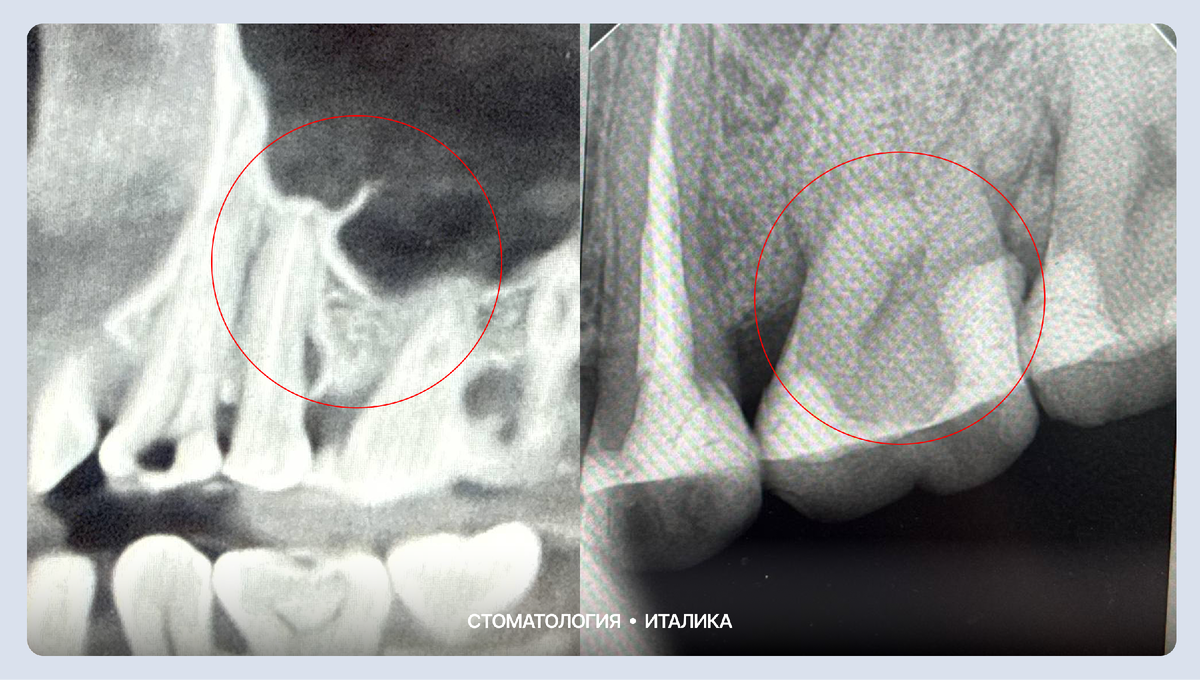

Просто вылечить каналы в такой ситуации недостаточно. Чтобы восстановить опору зуба и остановить процесс, потребовалось хирургическое вмешательство:

1. Очистка очага: Мы убрали все пораженные ткани и инфекцию внутри кости.

2. Костная пластика: Заполнили образовавшуюся полость специальным остеопластическим материалом (искусственной костью). Это фундамент, на котором вырастет своя здоровая ткань.

3. Работа с десной: Параллельно закрыли пародонтальные карманы у соседних зубов. Это предотвратит попадание новой инфекции и защитит корни от оголения.

На снимке справа видна плотная, заполненная структура. Костная ткань восстановлена, очаг воспаления ликвидирован. Теперь зуб снова имеет надежную опору и прослужит пациенту еще долгие годы.